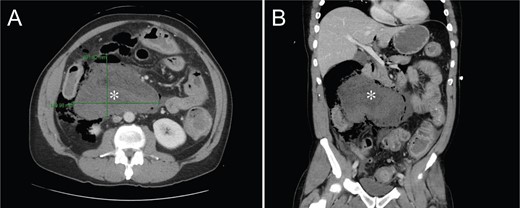

A computed tomography (CT) scan of the abdomen and pelvis showed a large fluid collection in the retroperitoneum abutting the right colon and duodenum, tracking into the right paracolic gutter, with associated pneumoperitoneum as well as free air within the retroperitoneum and mediastinum (Fig. 1).

CT of the abdomen and pelvis showing a 10.2 × 14.1 × 14.1 cm collection of stool, fluid and gas along the right colon.